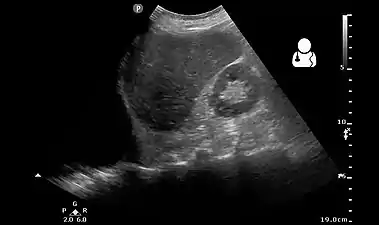

يُمكن استعمال التصوير بالموجات فوق الصوتية لتشخيصِ تدمي الصدر والانصبابات الجنبية الأُخرى، حيث يستعمل عادةً في حالات الرعاية المُكثفة ورعاية الإصابات؛ وذلك لأنها تُوفر نتائج موثوقة وسريعة بجانب سرير المريض.[8] يُعتبر التصوير بالموجات فوق الصوتية أكثر حساسية من تصوير الصدر بالأشعة السينية في تشخيص تدمي الصدر.[21]

تصوير صدري بالموجات فوق الصوتية يُظهرُ تدمي صدري على الجانب الأيسر